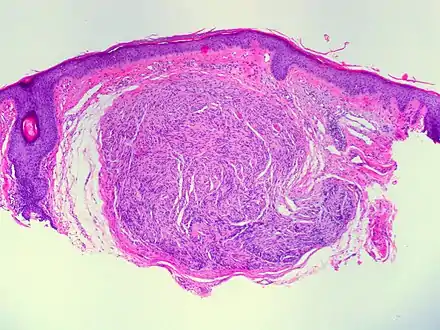

| Micrograph of a palisaded encapsulated neuroma | |

Palisaded and Encapsulated Neuroma